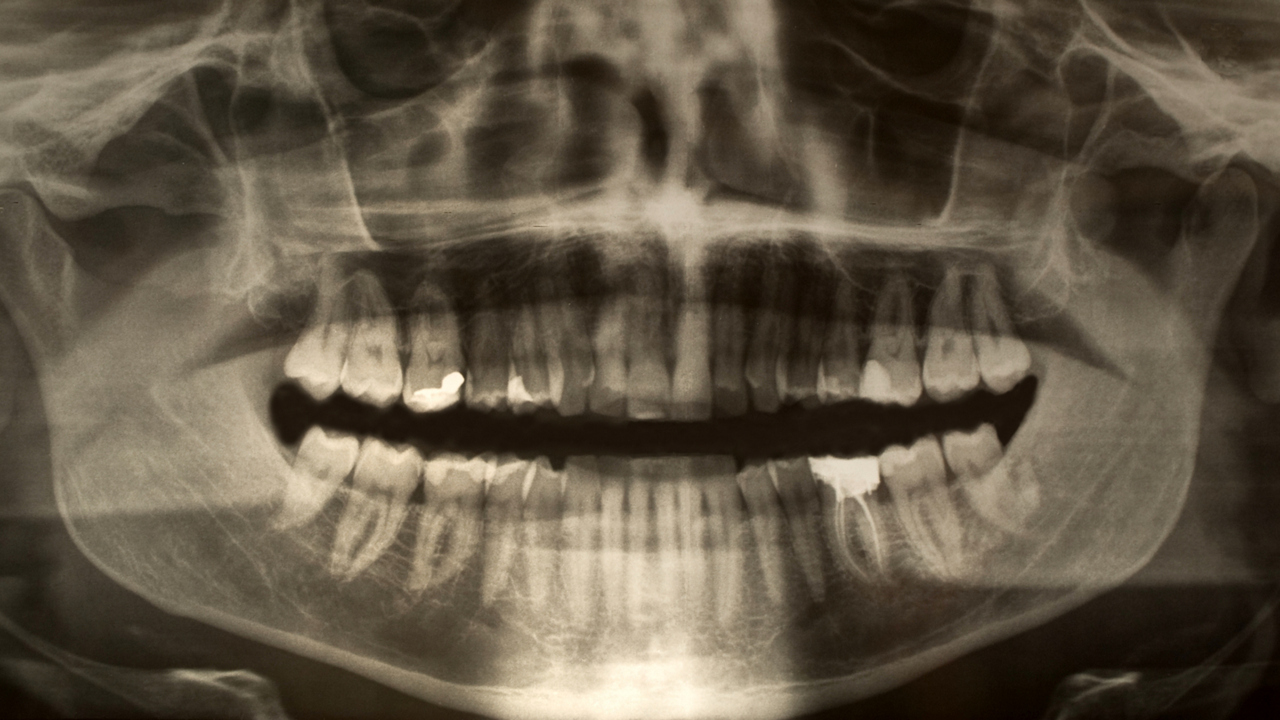

Röntgenbild på käke och tänder.

Infektionsbenägenhet och bakterieflora bakom karies

Individuell variation förklarar återkommande kariessjukdom och att andra är symptomfria.